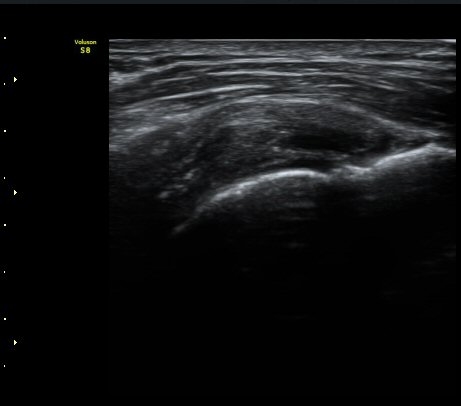

À̵ιڱ٠Á¾´Ü¸é°Ë»ç»ó ƯÀÌ ¼Ò°ßÀ» º¸ÀÌÁö ¾ÊÀ¸³ª(±×¸² 1)  ŽÃËÀÚ¸¦ ¾Æ·¡·Î À̵¿ÇÏ´Ï

°ß°©ÇÏ±Ù°Ç ³»Ãø¿¡¼­ ¼ö¾×Àú·ù°¡ °üÂûµÈ´Ù(±×¸² 2).